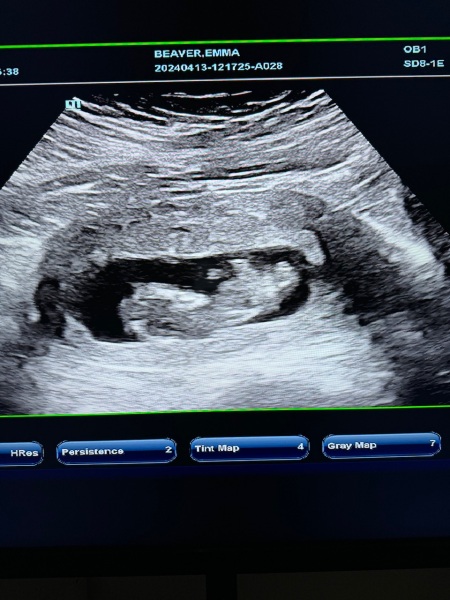

Just want to see what everyone is thinking ☺️

girl or boy 🩷🩵

12 weeks 2 days

@Chlaribo98 I'd be very surprised if that's not a boy!

Love the baby scans and @Chlaribo98 I'd say boy too!! 🩵